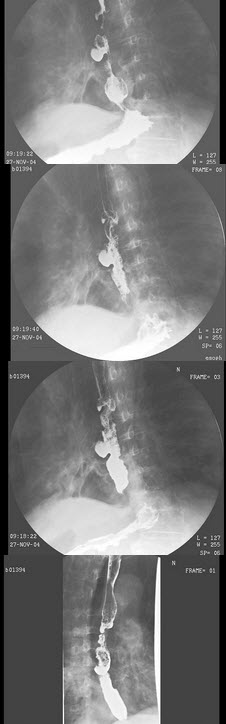

258、单项选择题

女,41岁,纺织工,腕部疼痛无力数周,结合CR和MR,最可能的诊断是()

A.月骨结核

B.月骨缺血坏死

C.骨质疏松

D.骨髓炎

E.骨软骨炎

259、多项选择题 副鼻窦瓦特氏位,不能观察到的影像有()